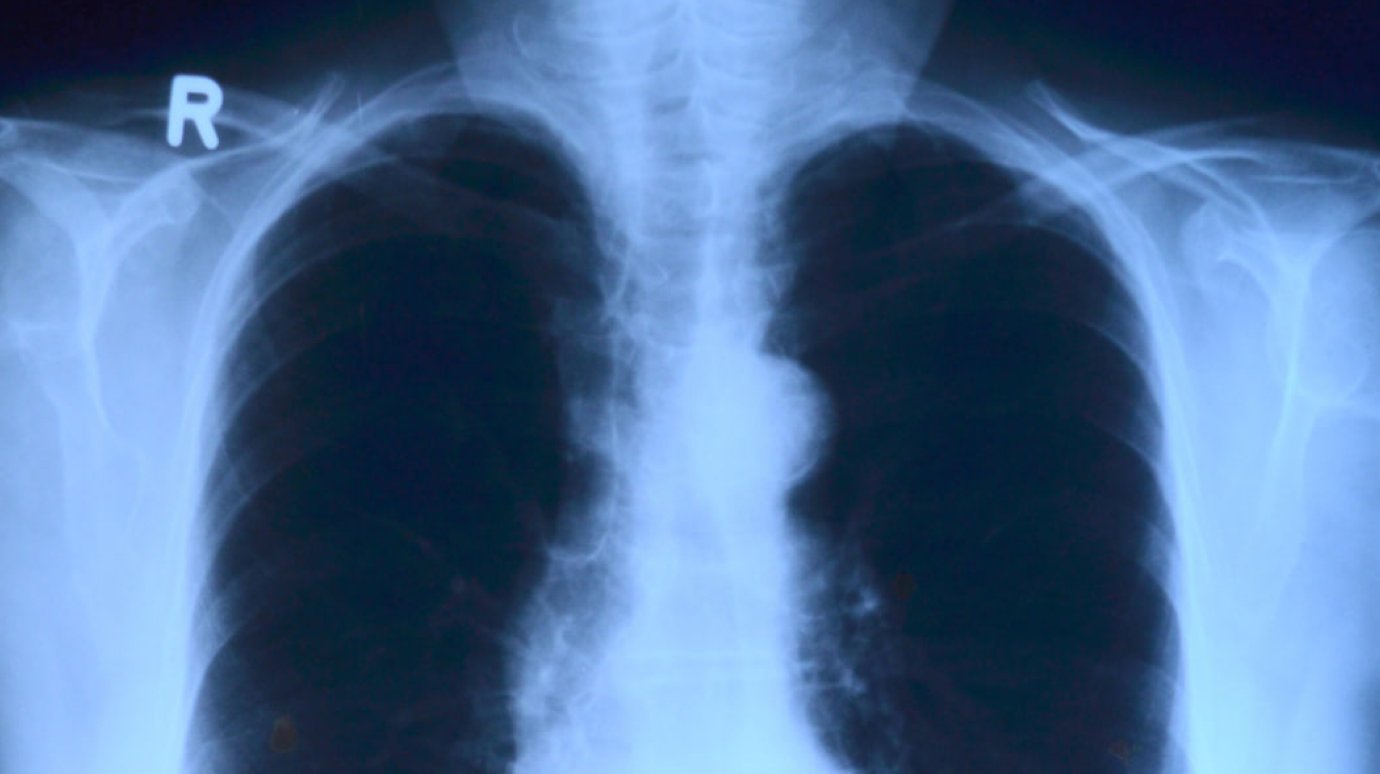

Специалист Минздрава заявил о непригодности флюорографии для диагностики рака легкого

Фото - penzainform.ru